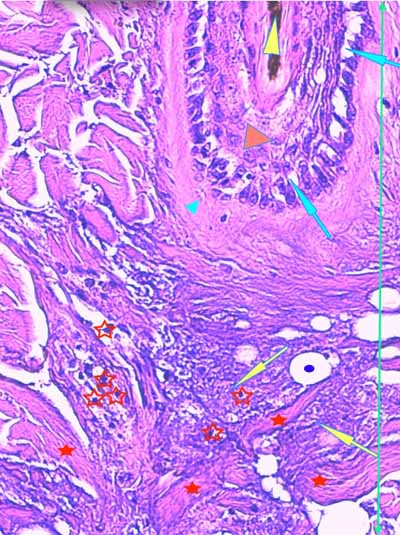

Photo 13 (Hémalun-Eosine X200) : dans le derme, on remarque des plages

cellulaires inflammatoires, peuplées de granulocytes neutrophiles,

en étroit rapport avec les unités annxielles folliculo-sébacées.

Légendes de la Photo 13 :

- Étoiles rouges vides : glandes sébacées

- Étoiles rouges pleines : follicules pileux

- Pointe de flèche jaune : canal pilaire

- Flèches turquoises : plage cellulaire inflammatoire peuplée de cellules pycnotiques et de granulocytes neutrophiles

- Double flèche verte : derme

Photo 14 (Hémalun-Eosine X100) : à la jonction dermo-hypodermique,

un bulbe folliculaire anormal est en rapport direct avec une plage cellulaire inflammatoire.

Légendes de la Photo 14 :

- Étoile rouge vide : adipocyte

- Étoiles rouges pleines : vaisseaux sanguins (une erreur au milieu à droite = adipocyte)

- Pointe de flèche jaune : reliquat de bulbe pilaire fracturé et désolidarisé du reste du follicule pileux

- Flèches turquoises : plage cellulaire inflammatoire peuplée de cellules pycnotiques et de granulocytes neutrophiles, en étroit rapport avec le reliquat de bulbe folliculaire

- Double flèche bleue : hypoderme